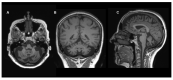

Coenzyme Q10 (CoQ10) is an endogenously synthesized lipid molecule. It is best known for its role as a cofactor within the mitochondrial respiratory chain where it functions in electron transfer and ATP synthesis. However, there are many other cellular pathways that also depend on the CoQ10 supply (redox homeostasis, ferroptosis and sulfide oxidation). The CoQ10 biosynthesis pathway consists of several enzymes, which are encoded by the nuclear DNA. The majority of these enzymes are responsible for modifications of the CoQ-head group (benzoquinone ring). Only three enzymes (PDSS1, PDSS2 and COQ2) are required for assembly and attachment of the polyisoprenoid side chain. The head-modifying enzymes may assemble into resolvable domains, representing COQ complexes. During the last two decades, numerous inborn errors in CoQ10 biosynthesis enzymes have been identified. Thus far, 11 disease genes are known (PDSS1, PDSS2, COQ2, COQ4, COQ5, COQ6, COQ7, COQ8A, COQ8B, COQ9 and HPDL). Disease onset is highly variable and ranges from the neonatal period to late adulthood. CoQ10 deficiency exerts detrimental effects on the nervous system. Potential consequences are neuronal death, neuroinflammation and cerebral gliosis. Clinical features include encephalopathy, regression, movement disorders, epilepsy and intellectual disability. Brain magnetic resonance imaging (MRI) is the most important tool for diagnostic evaluation of neurological damage in individuals with CoQ10 deficiency. However, due to the rarity of the different gene defects, information on disease manifestations within the central nervous system is scarce. This review aims to provide an overview of brain MRI patterns observed in primary CoQ10 biosynthesis disorders and to highlight disease-specific findings.